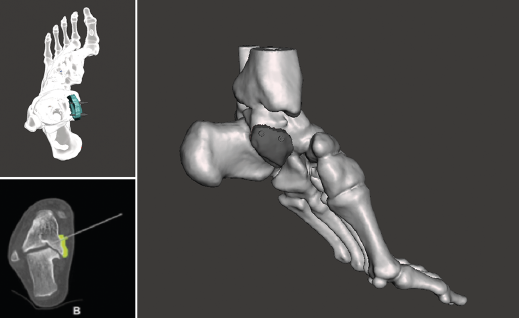

Figura 1. Fractura conminuta de la cúpula del astrágalo.

Se trata de un paciente varón de 35 años que, tras una precipitación, presenta impotencia funcional en el miembro inferior. Tras la valoración clínica y radiológica, se observa un estallido de la parte posterior de la cúpula astragalina (Figura 1).

Utilidad de la impresión 3D: debido a la complejidad de la lesión, se decide tratarla con un aloinjerto estructural. Se decidió imprimir un modelo 3D del defecto óseo para poder tallar el injerto con la forma más parecida al defecto original.

- Obtención de la forma real del defecto combinando el astrágalo con una imagen especular del astrágalo contralateral (Figura 2).

- Impresión 3D del defecto del astrágalo y guía para la colocación de las agujas (Figura 3).